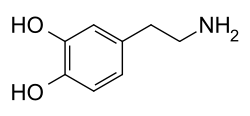

Dopamine (DA, a contraction of 3,4-dihydroxyphenethylamine) is a neuromodulatory molecule that plays several important roles in cells. It is an organic chemical of the catecholamine and phenethylamine families. Dopamine constitutes about 80% of the catecholamine content in the brain. It is an amine synthesized by removing a carboxyl group from a molecule of its precursor chemical, L-DOPA, which is synthesized in the brain and kidneys. Dopamine is also synthesized in plants and most animals. In the brain, dopamine functions as a neurotransmitter—a chemical released by neurons (nerve cells) to send signals to other nerve cells. Neurotransmitters are synthesized in specific regions of the brain, but affect many regions systemically. The brain includes several distinct dopamine pathways, one of which plays a major role in the motivational component of reward-motivated behavior. The anticipation of most types of rewards increases the level of dopamine in the brain,[4] and many addictive drugs increase dopamine release or block its reuptake into neurons following release.[5] Other brain dopamine pathways are involved in motor control and in controlling the release of various hormones. These pathways and cell groups form a dopamine system which is neuromodulatory.[5]

Structure

A dopamine molecule consists of a catechol structure (a benzene ring with two hydroxyl side groups) with one amine group attached via an ethyl chain.[15] As such, dopamine is the simplest possible catecholamine, a family that also includes the neurotransmitters norepinephrine and epinephrine.[16] The presence of a benzene ring with this amine attachment makes it a substituted phenethylamine, a family that includes numerous psychoactive drugs.[17]